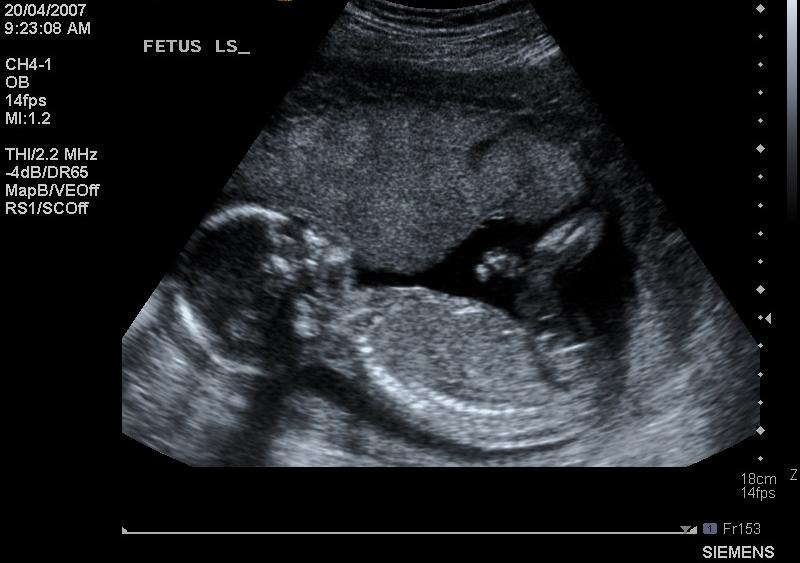

As producers of remembrance photo frames, we are especially supportive of this event and recognise the importance of a photo to preserve memories and to offer a powerful image that is emotive and important. While it is not something we ever want to do, we know that offering parents a way to capture their child in photographic form forever can help in the grieving process and we are humbled to be a small part in that.